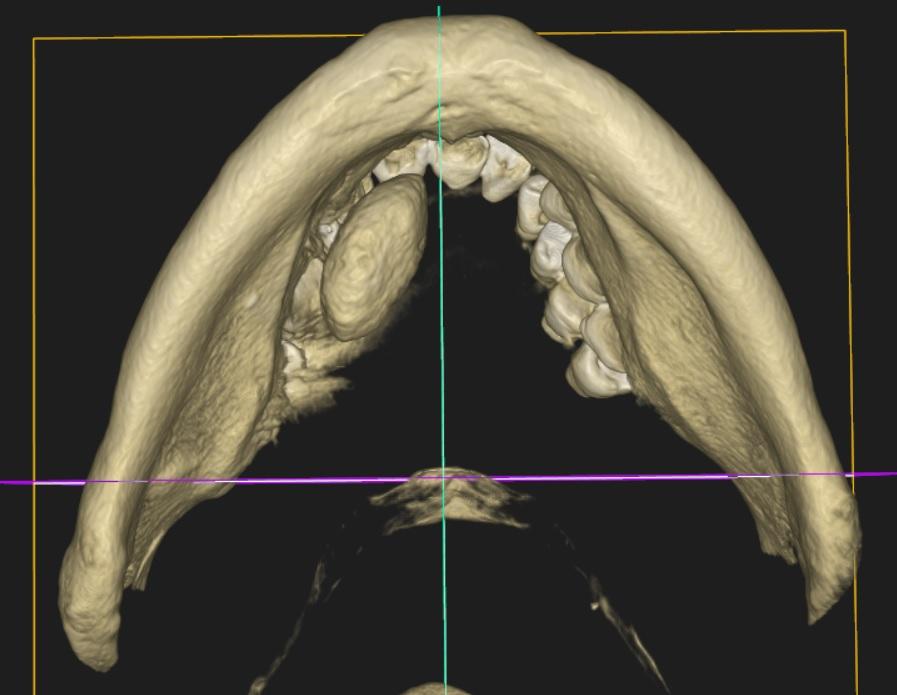

Tomografia CBCT żuchwy

W dnie jamy ustnej po stronie prawej, na wysokości trzonu żuchwy od 43-46 widoczne trójwymiarowe zaciemnienie owalnego kształtu, o wymiarach 21,9/10,4/13,5mm. Bez kontaktu z kością żuchwy, wysyceniem odpowiadające tkankom twardym. Wewnątrz widoczne tarczki, świadczące o budowie warstwowej. Z uwagi na umiejscowienie można podejrzewać kamień w śliniance. Zalecane badanie USG i/lub sialografia po konsultacji z chirurgiem.